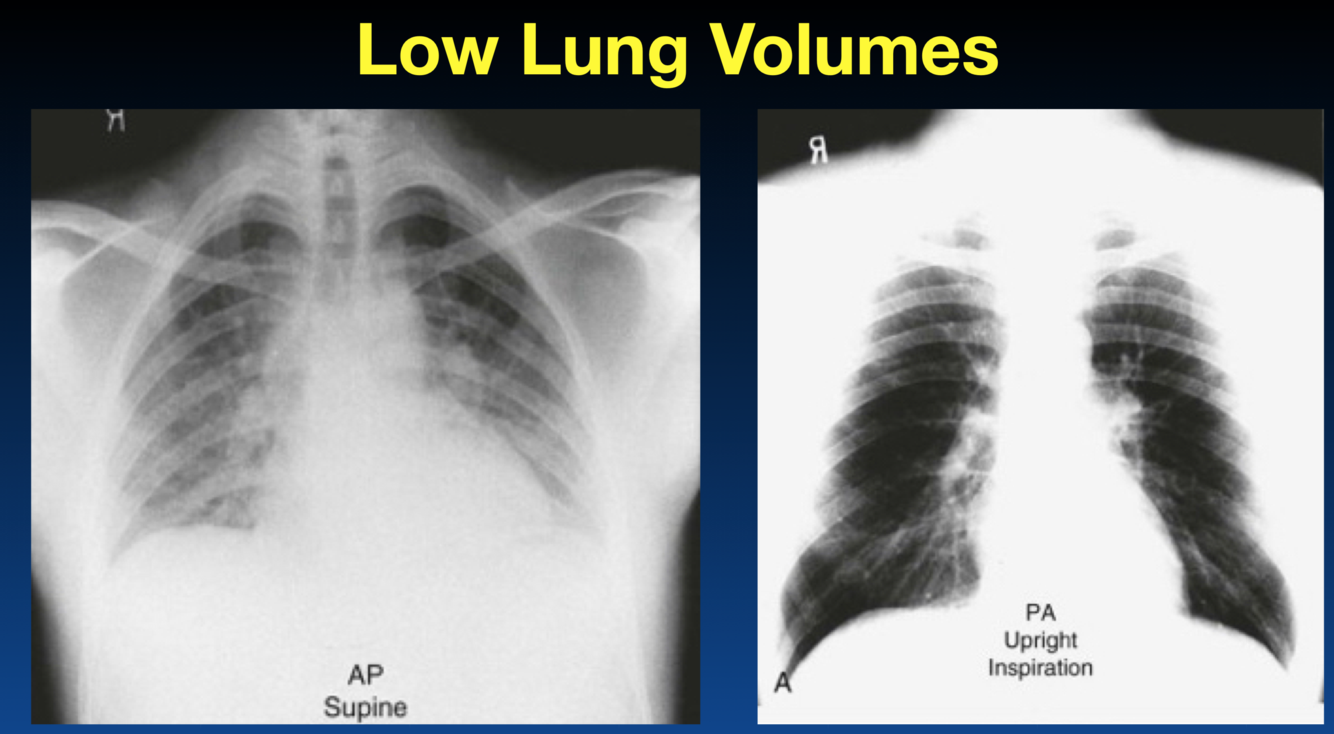

This does not show a real increase CTR. Why?

You can tell an expiration by the height of diaphragm as well as counting the ribs (the right only shows 4 ribs). You should see 6 or 7 ribs.